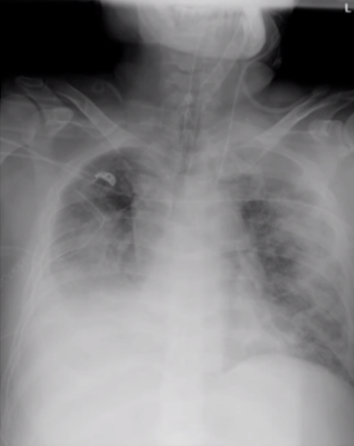

患者胸部X线片可见,除了右肺受累,左肺也可见磨玻璃样渗出影;氧合下降。4月9日胸部X线片可见明显空腔,PaCO2急剧升高,病情加重(图4)

图片

图4  患者胸部X线片和氧合变化情况